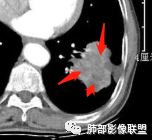

右肺下叶背段实变影,宽基底与胸膜相连,边缘毛糙,内部可见空洞影,空洞壁光滑,内部可见坏死,近端支气管显示不清,远端胸膜下间隙可见,青年男性,考虑结核,鉴别NTM,鳞癌

青年男性,呼吸道症状起病,右肺下叶背段肉芽肿样变,边缘分叶,胸膜糊墙,略牵拉,内部密度不均,空洞无物,壁整,支气管通畅,卫星灶,玫瑰结状小叶中心性结节及少量树芽;中度强化,湖泊样坏死,内部无完整血管影:结核可能性、鉴别:坏死性支原体肺炎、鳞癌。

有晕征,第一感觉像是感染类病变,仔细看下叶支气管不通畅,感觉有阻塞,先考虑感染类病变,肺链?隐球?毛霉曲霉?TB?NTM?鉴别诊断肉瘤类,肉瘤样癌,类癌。

青年,咳嗦,指标基本正常,右肺下叶不规则软组织密度影,密度不均,有坏死,小空洞,宽基底与胸膜相连,支气管觉得通畅,考虑感染,鉴别结核

35岁男性患者,病史及实验室检查无免疫受损相关依据,无感染毒血症状,炎症指标CRP、降钙素原、血沉均正常,曲霉抗原阴性;CT提示右下背段肿块影,边缘膨隆,有分叶及短毛刺,偏心空洞,增强扫描提示不均匀强化,有坏死,考虑:1.腺癌 2.隐球

中年男性,咳嗽2月余,pct正常,首先排除普通肺炎。右下背段肿块,边缘毛糙,浅分叶,与胸膜宽基底相连,有坏死(无液平,为凝固性坏死,不考虑脓肿),常规考虑结核隐球菌,鉴别恶性肿瘤

青年男性患者,间断咳嗽、少量黄白痰2月,胸部CT:右肺下叶后基底段类圆形病灶,边界清楚,周围磨玻璃,内部有空洞形成,空洞干净,考虑炎性病变,脓肿,隐球,结核,鉴别鳞癌

右肺下叶肿块,分叶,近端支气管部分堵塞,部分沿壁厚,沼泽样强化,可见空洞,邻近胸膜少量积液,膈肌牵拉,考虑肿瘤,鳞癌?鉴别NTM

青年男性,慢性病程,右肺下叶团块影,形态不规则,内见空洞,壁厚薄不均,不均匀轻度强化。考虑恶性,肺癌,肿标中角蛋白19增高,倾向于鳞癌,鉴别结核。

中年男性,有咳嗽咳痰病史俩月,亚急性病程,炎性指标不高,右肺下叶后基底段近胸膜下不规则肿块,边缘膨隆毛糙,支气管近端阻塞,内有厚壁空洞,无液平,洞壁不均匀强化,周围支气管壁厚,远端有点片影,考虑鳞癌可能性大,鉴别肺脓肿和肺结核。但是血沉不快,crp不高,有点不大符合炎性。